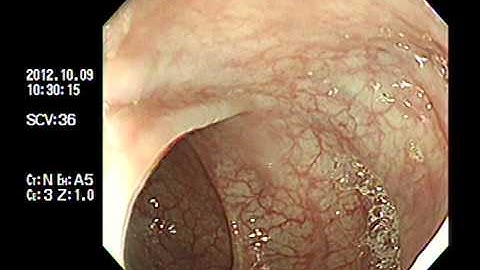

Cắt polyp đại tràng Qua Nội Soi | Colonoscopic Polypectomy